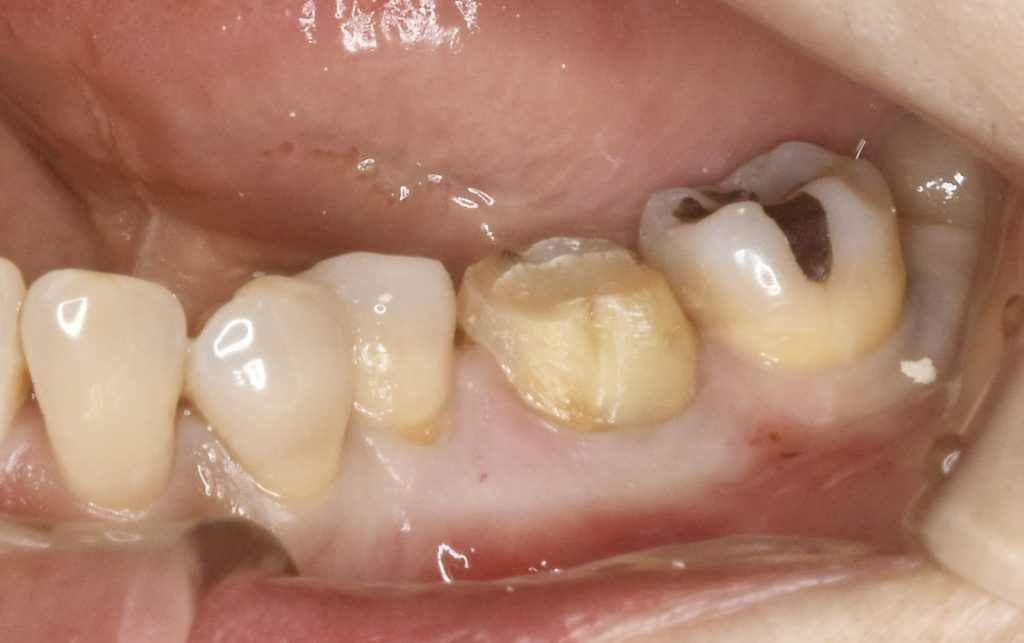

下記の症例は奥歯の抜歯と同時にインプラント治療を行った術後になります。

安全なインプラント治療を提供する為に、SMOPガイドシステムを活用し、術中の痛みやストレスをコントロールする為に麻酔科医による鎮静麻酔を依頼しました。